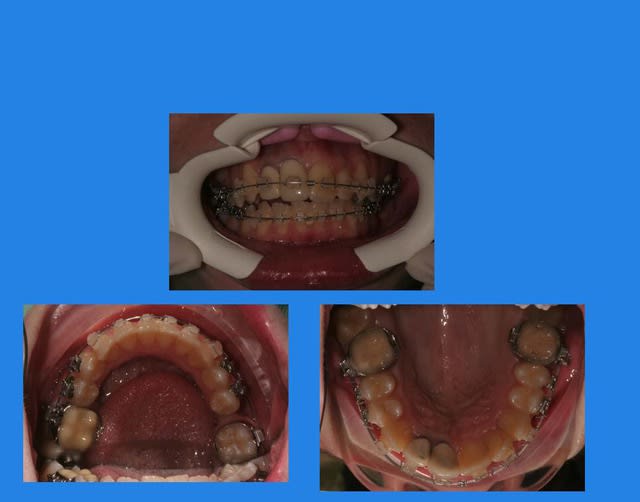

Début du cas :

pose mat Sup.

1 q4hjp9 - Eugenol

1 p3qrc4 - Eugenol

Bjc.

13/03/2010 à 23h42

4mois après, comme ça n’avance pas vite, pose Q.H

et pose du mat. Inf.

2 wqai8e - Eugenol

contrôle 3 semaines après

3 m607iq - Eugenol

13/03/2010 à 23h44

Puis elle ne vient pas pendant plus de 2 mois

et, oh surprise (mauvaise)

c’est la cata !!!

4 pzmuzx - Eugenol

Images 1 qtgoxf - Eugenol